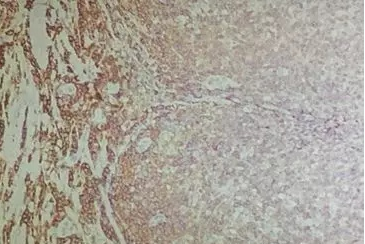

彌散性非特異性背景,可能是由內(nèi)源性過(guò)氧化物酶引起的(如圖2)。因此,封閉液要現(xiàn)配現(xiàn)用,充分封閉,一般15min。

二、內(nèi)源性過(guò)氧化物酶